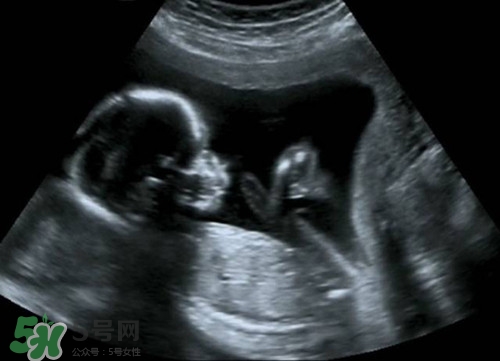

懷孕之后b超肯定是要做的,那么懷孕多久后可以做b超呢?做b超的話(huà)會(huì)影響到孩子嗎?下面我們來(lái)一起介紹下吧!

意見(jiàn)建議:孕期一般做3-5次B超,孕早期一次,目的是為了確定妊娠,估計(jì)胚胎發(fā)育,診斷孕早期常見(jiàn)疾病如宮外孕,葡萄胎,各種類(lèi)型的流產(chǎn).孕中期也就是孕22-26周做四維彩超排畸篩查看看胎兒有無(wú)大體畸形及主要臟器畸形.孕晚期看胎兒,羊水及胎盤(pán)情況.

孕期做B超檢查是很有必要的.但是孕期做B超不要超過(guò)3次.一般是懷孕早期應(yīng)通過(guò)B超確定宮內(nèi)的妊娠是否正常.一般提倡于懷孕早期通過(guò)做B超明確是否是宮內(nèi)正常妊娠或雙胎,葡萄胎等.懷孕中期,大約在閉經(jīng)16周左右需要再做一次B超,以確定胎兒有無(wú)畸形和生長(zhǎng)發(fā)育是否正常.因?yàn)槿绻@時(shí)發(fā)現(xiàn)胎兒不正常,在閉經(jīng)20周以?xún)?nèi)中止妊娠,是比較適宜的.懷孕晚期,即閉經(jīng)36周以后,做B超可以明確羊水多少以及胎盤(pán)的功能.羊水過(guò)多或過(guò)少,以及胎盤(pán)鈣化或功能不良,都不應(yīng)再繼續(xù)妊娠.必要時(shí)需進(jìn)行剖腹產(chǎn)

正常情況下,妊娠早期應(yīng)進(jìn)行一次B超檢查,以明確是否妊娠,并確定妊娠的天數(shù).